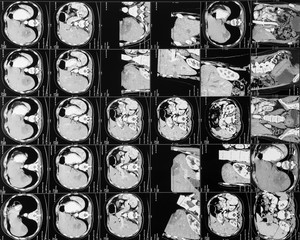

x-ray film..

x-ray film